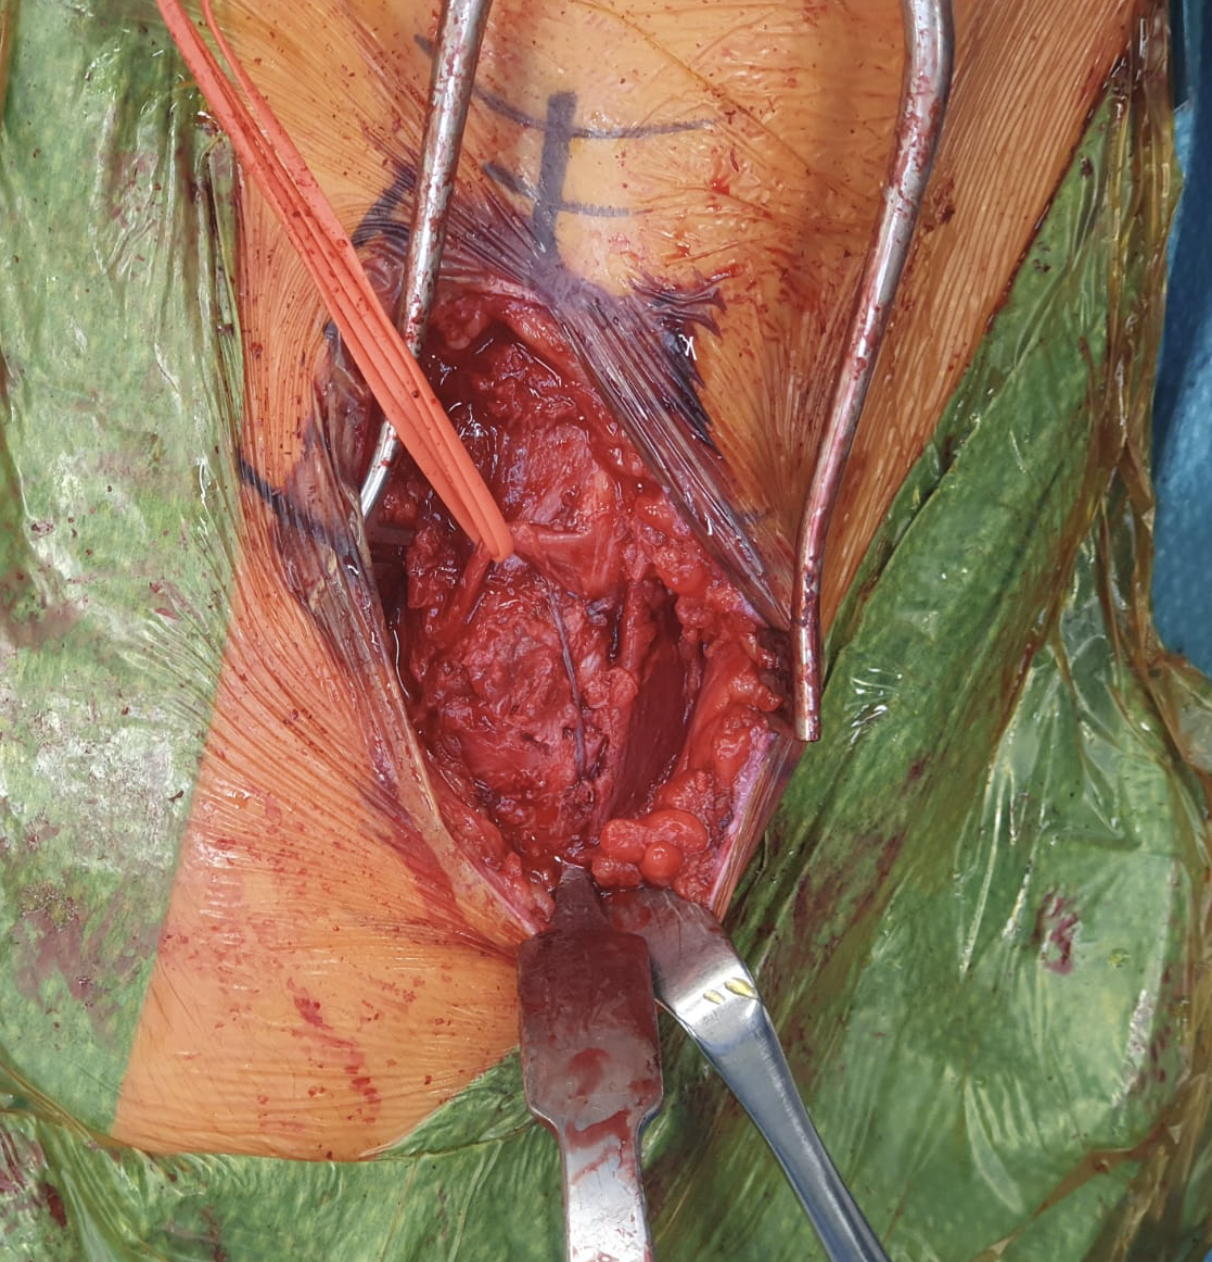

Technique

Surgical technique PDF ASIS avulsion

ASIS surgery